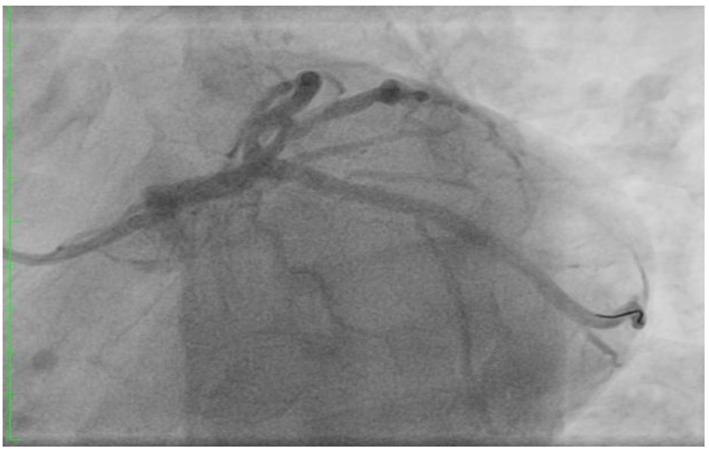

Although most of the patients presenting with ischemic heart disease have chest pains, there are other rare presenting symptoms like cardiac cephalgia. In this report, we present a case of acute coronary syndrome with an only presentation of exertional headache. It was postulated as acute presentation of coronary artery disease, due to previous history of similar presentation associated with some chest pains with previous left coronary artery stenting. We present an unusual case with cardiac cephalgia in a young patient under the age of 50 which was not reported at that age before. There are four suggested mechanisms for this cardiac presentation.

虽然大多数缺血性心脏病患者会出现胸痛,但也有其他罕见的症状,如心源性头痛。在本报告中,我们介绍了一例急性冠状动脉综合征,其唯一表现为劳力性头痛。由于既往有类似表现且伴有胸痛,曾行左冠状动脉支架置入术,故推测为冠状动脉疾病的急性表现。我们报告了一例50岁以下年轻患者的心源性头痛的罕见病例,此前该年龄段未见报道。关于这种心脏表现有四种推测机制。